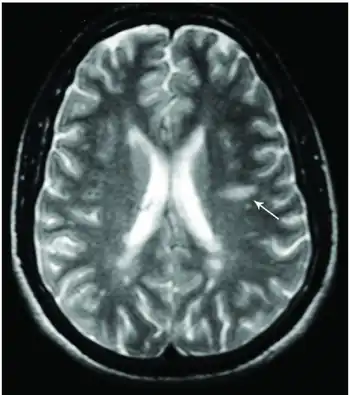

Dawson's Fingers appearing on an MRI scan

This morphologic appearance was named Dawson's fingers by Charles Lumsden, after the Scottish pathologist James Walker Dawson,[31] who first defined the condition in 1916.

Dawson's fingers

Image shows multiple lesions in periventricular and subcortical white matter, Dawson's finger is a characteristic finding in multiple sclerosis

"Dawson's fingers" is the name for the lesions around the ventricle-based brain veins[32][33] of patients with multiple sclerosis and antiMOG associated encephalomyelitis[34]

Though once thought to be specific of MS, it is known not to be the case.[35]

The condition is thought to be the result of inflammation or mechanical damage by blood pressure[30] around long axis of medular veins.

Dawson's fingers spread along, and from, large periventricular collecting veins, and are attributed to perivenular inflammation.[36]

Lesions far away from these veins are known as Steiner's splashes.[30]